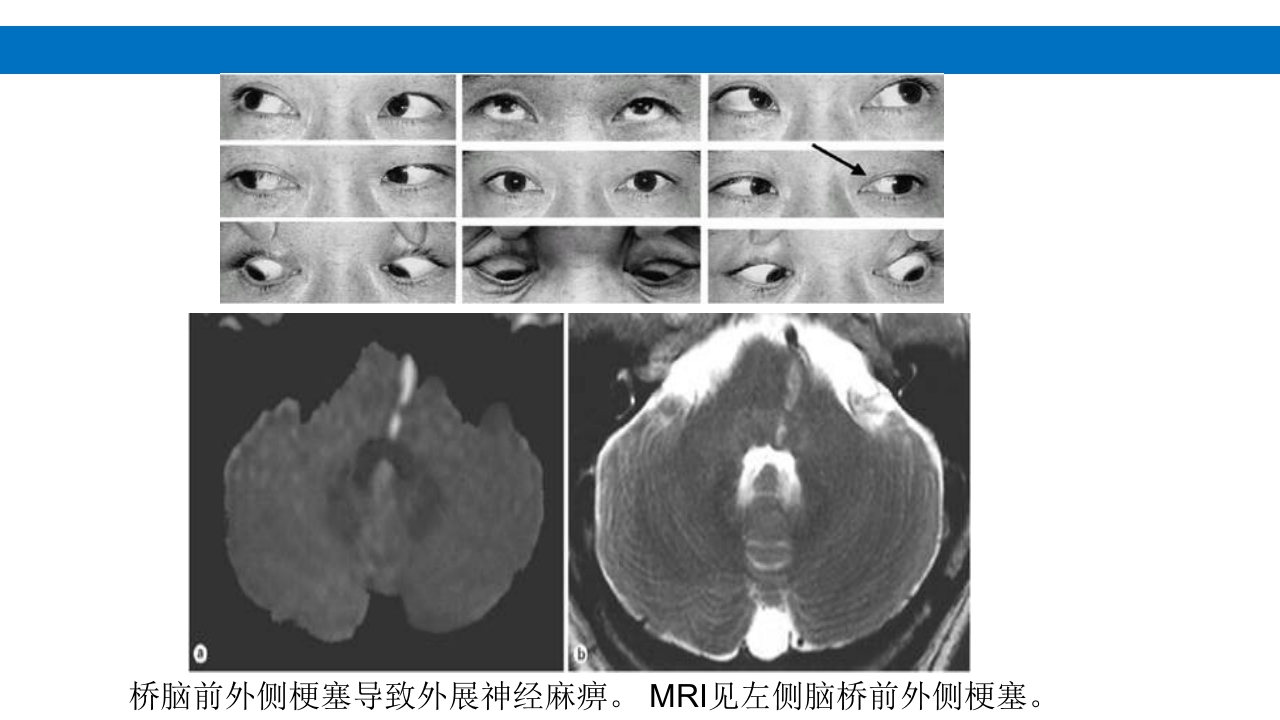

颅脑损伤的并发症及后遗症 讲解人:xxx 20XX年x月x日 1.颅骨骨髓炎 病因:为头皮软组织、中耳、乳突和副鼻窦等处炎性感染而经导 血管侵入颅骨内或颅脑开放伤感染所引起,亦可由菌血症后发生 的细菌栓子由血运转移至颅骨内。 影像学表现: 头部CT: 1.表现为不规则的蜂窝状骨质破坏区,主要位于板障,亦可累 及内外板。 2.破坏区内可见高密度的米粒状细小的高密度死骨。 3.周边可见骨质硬化增生,颅板外无骨膜反应。 4.局部的头皮可见软组织肿胀。 头部MRI: 由于受累部位细胞成分和水量增多,T1WI为低信号, T2WI为高信号,急性期边界不清,慢性期病灶局限, 边界清晰。MRI显示骨质破坏没有CT效果好。 治疗: 除应用抗菌药物控制感染外,当感染局限或已有死骨形成后, 应行手术切除感染...